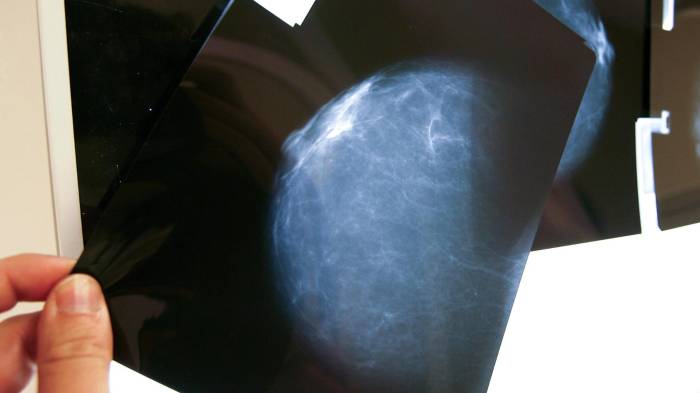

“El autoexamen no es para detectar el cáncer, sino para reconocer la normalidad del cuerpo. Las mamografías y ecografías son las que salvan vidas”, enfatizó, tras subrayar la importancia de integrar la educación sanitaria en las escuelas para crear adultos más conscientes de su salud.Por su parte, el legislador mexicano Éctor Jaime Ramírez planteó que la región requiere “una gran reforma digital en salud” que permita contar con expedientes clínicos electrónicos.